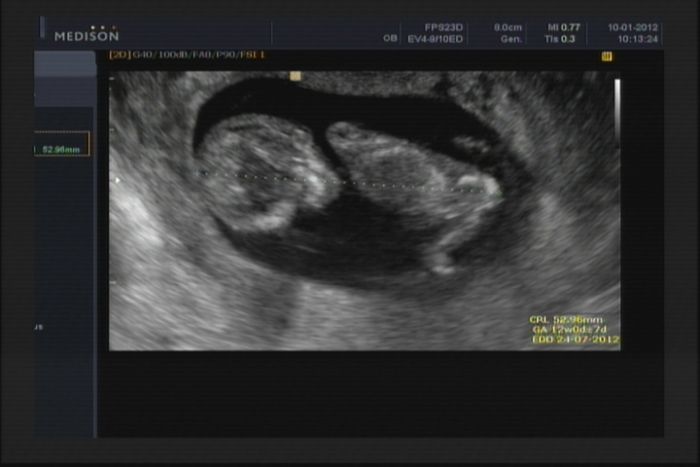

Tak jsme dneska dopadli dobře, krevní testy vše super, dostali jsme knížku a řítíme se do 4 měsíce !

Fotka trošku rozmazaná ale je vidět dobře ...

Ahoj holky, tak já dopadla taky super..krev i sono naprosto v pořádku. 31.1. jdu znovu na krev a pak za týden na další sono..přijde mi to brzy, ale doktor asi ví, co dělá a já budu mít jistotu, že je vše ok :-)

Autor: Verča 10.1.2012 v 18:53

Jéé všimla jsem si, že jsem tam dala špatné datum, ale je to z dneška :-).